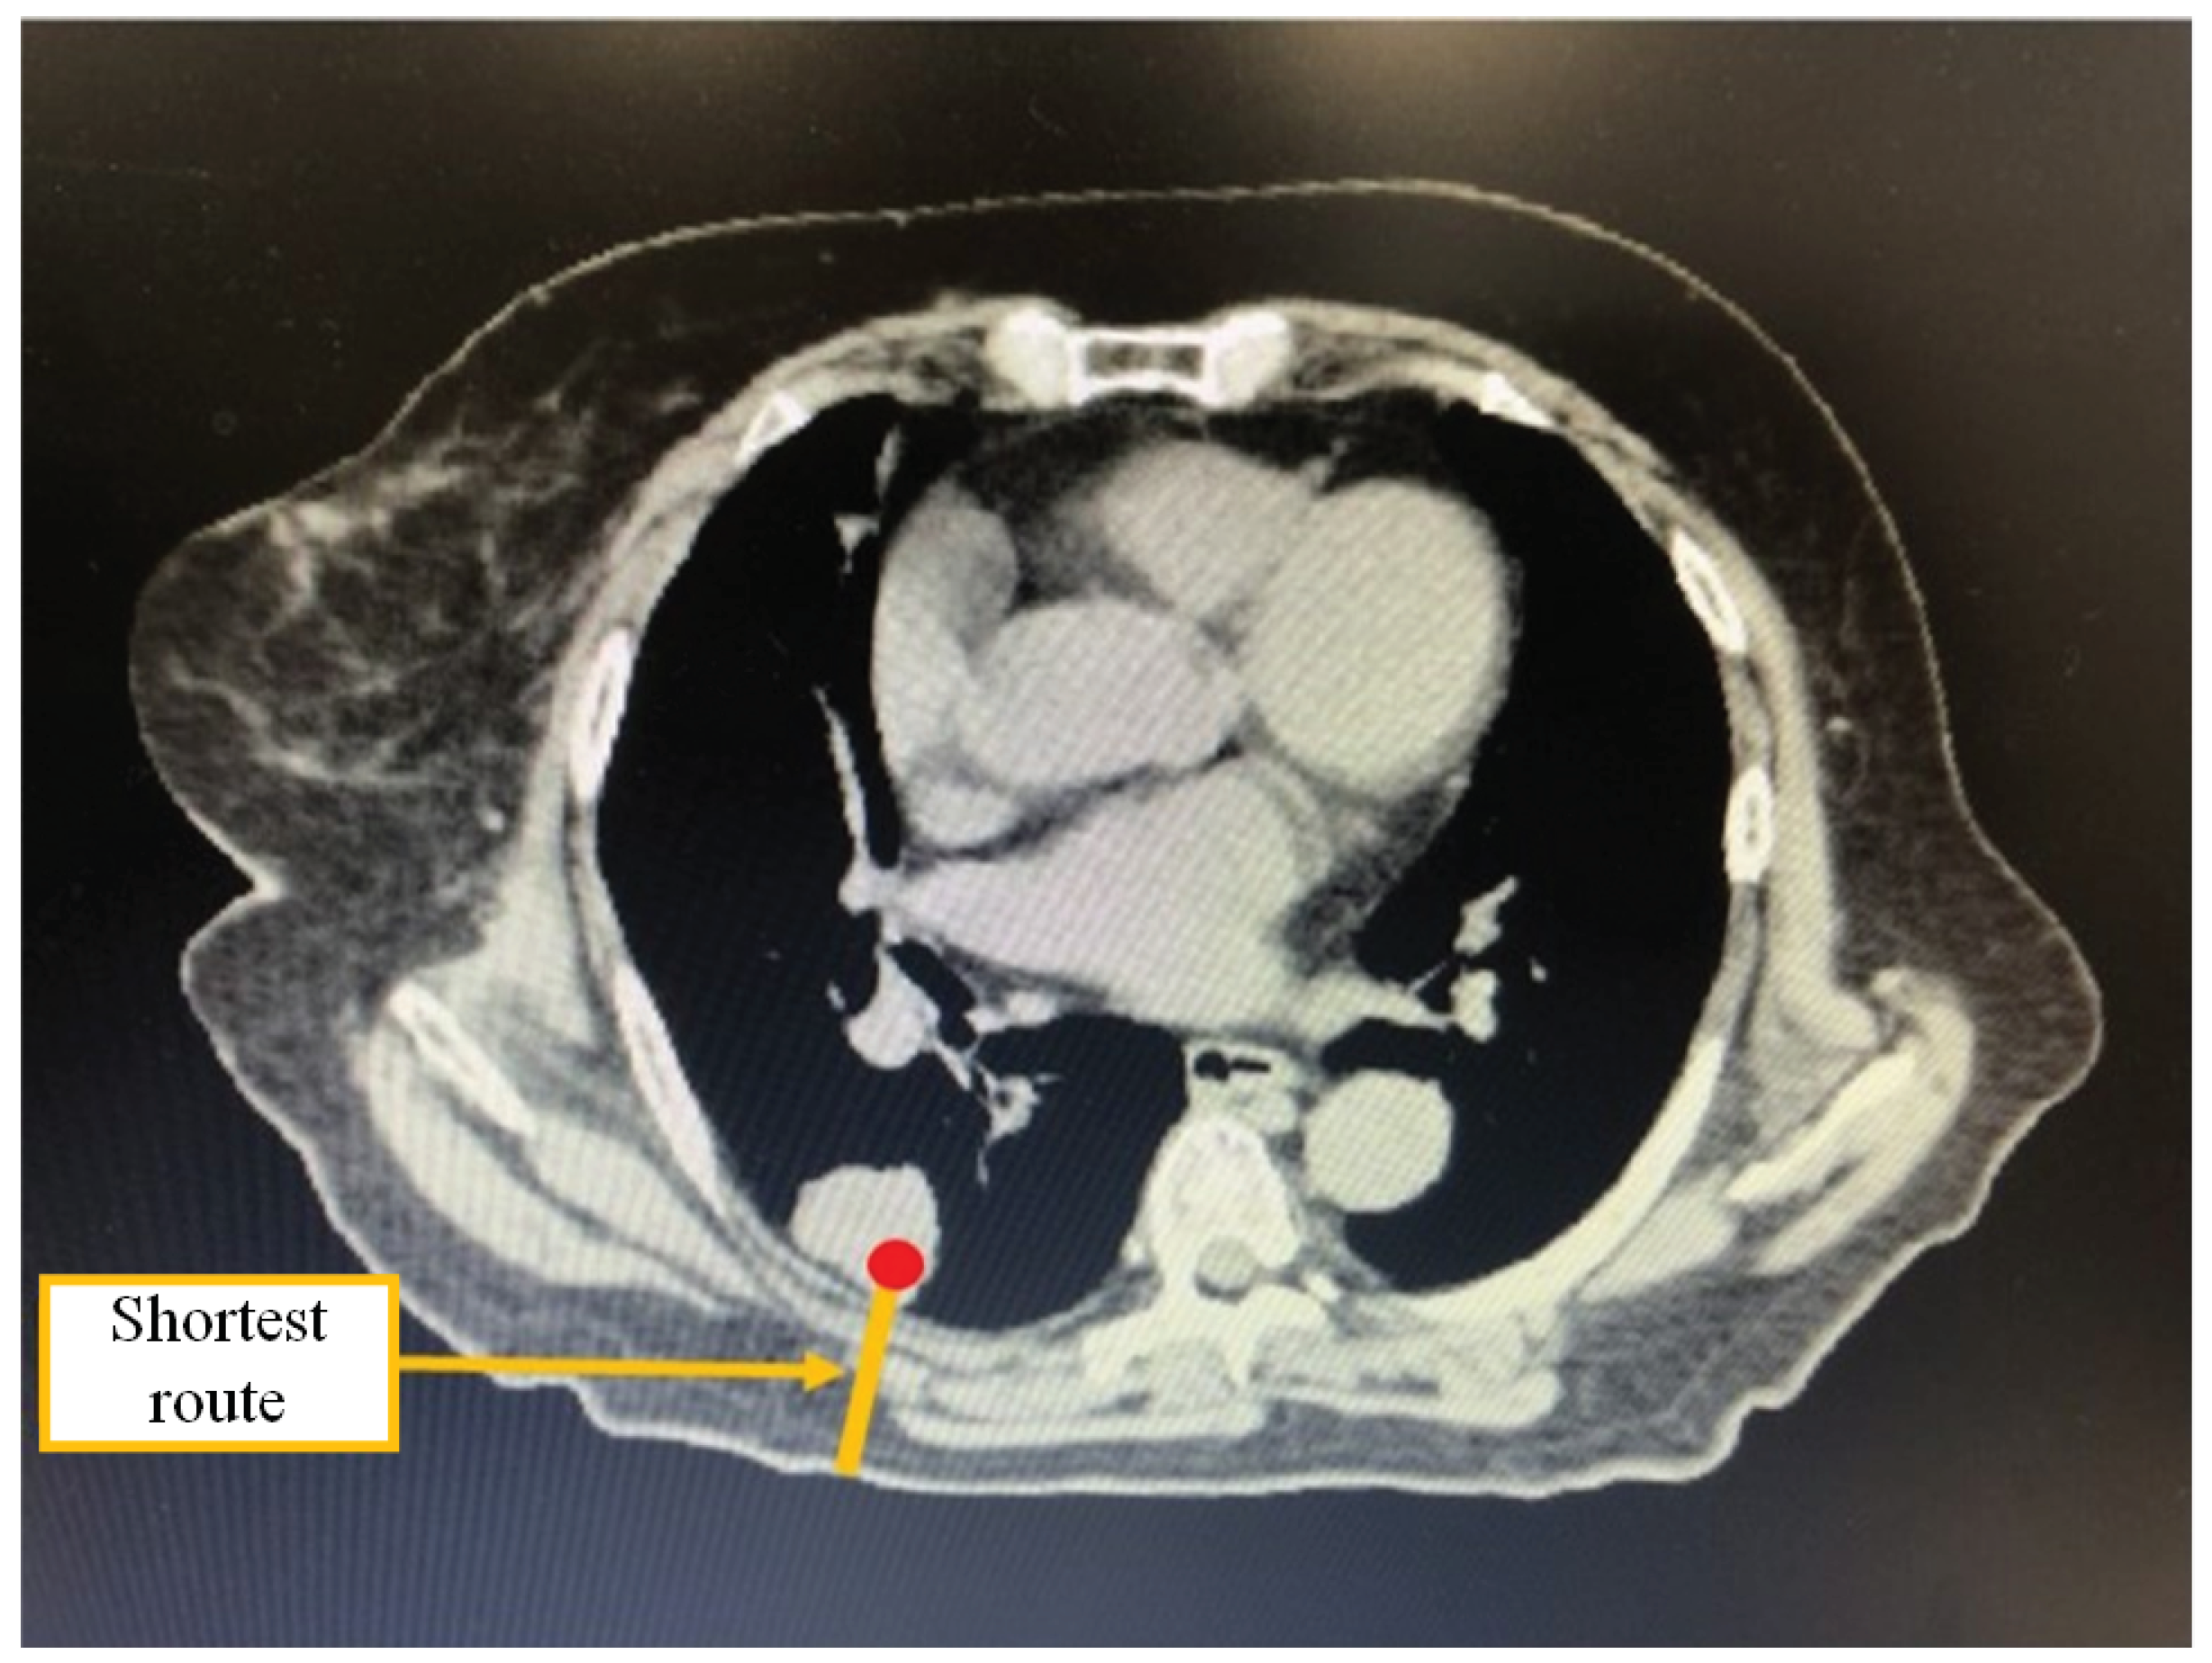

An example of the shortest route in a CT image puncture is shown in Figure 2. The shortest route among multiple puncture routes from the pixel containing the coordinates of the target indicated by the red circle to the pixel in contact with the air outside the body is shown. By selecting the shortest route, the physician can shorten the puncture time and reduce the radiation dose from the CT scan during the actual puncture.

Figure 2. Example of displaying the shortest route.

Jimaging 10 00251 g002